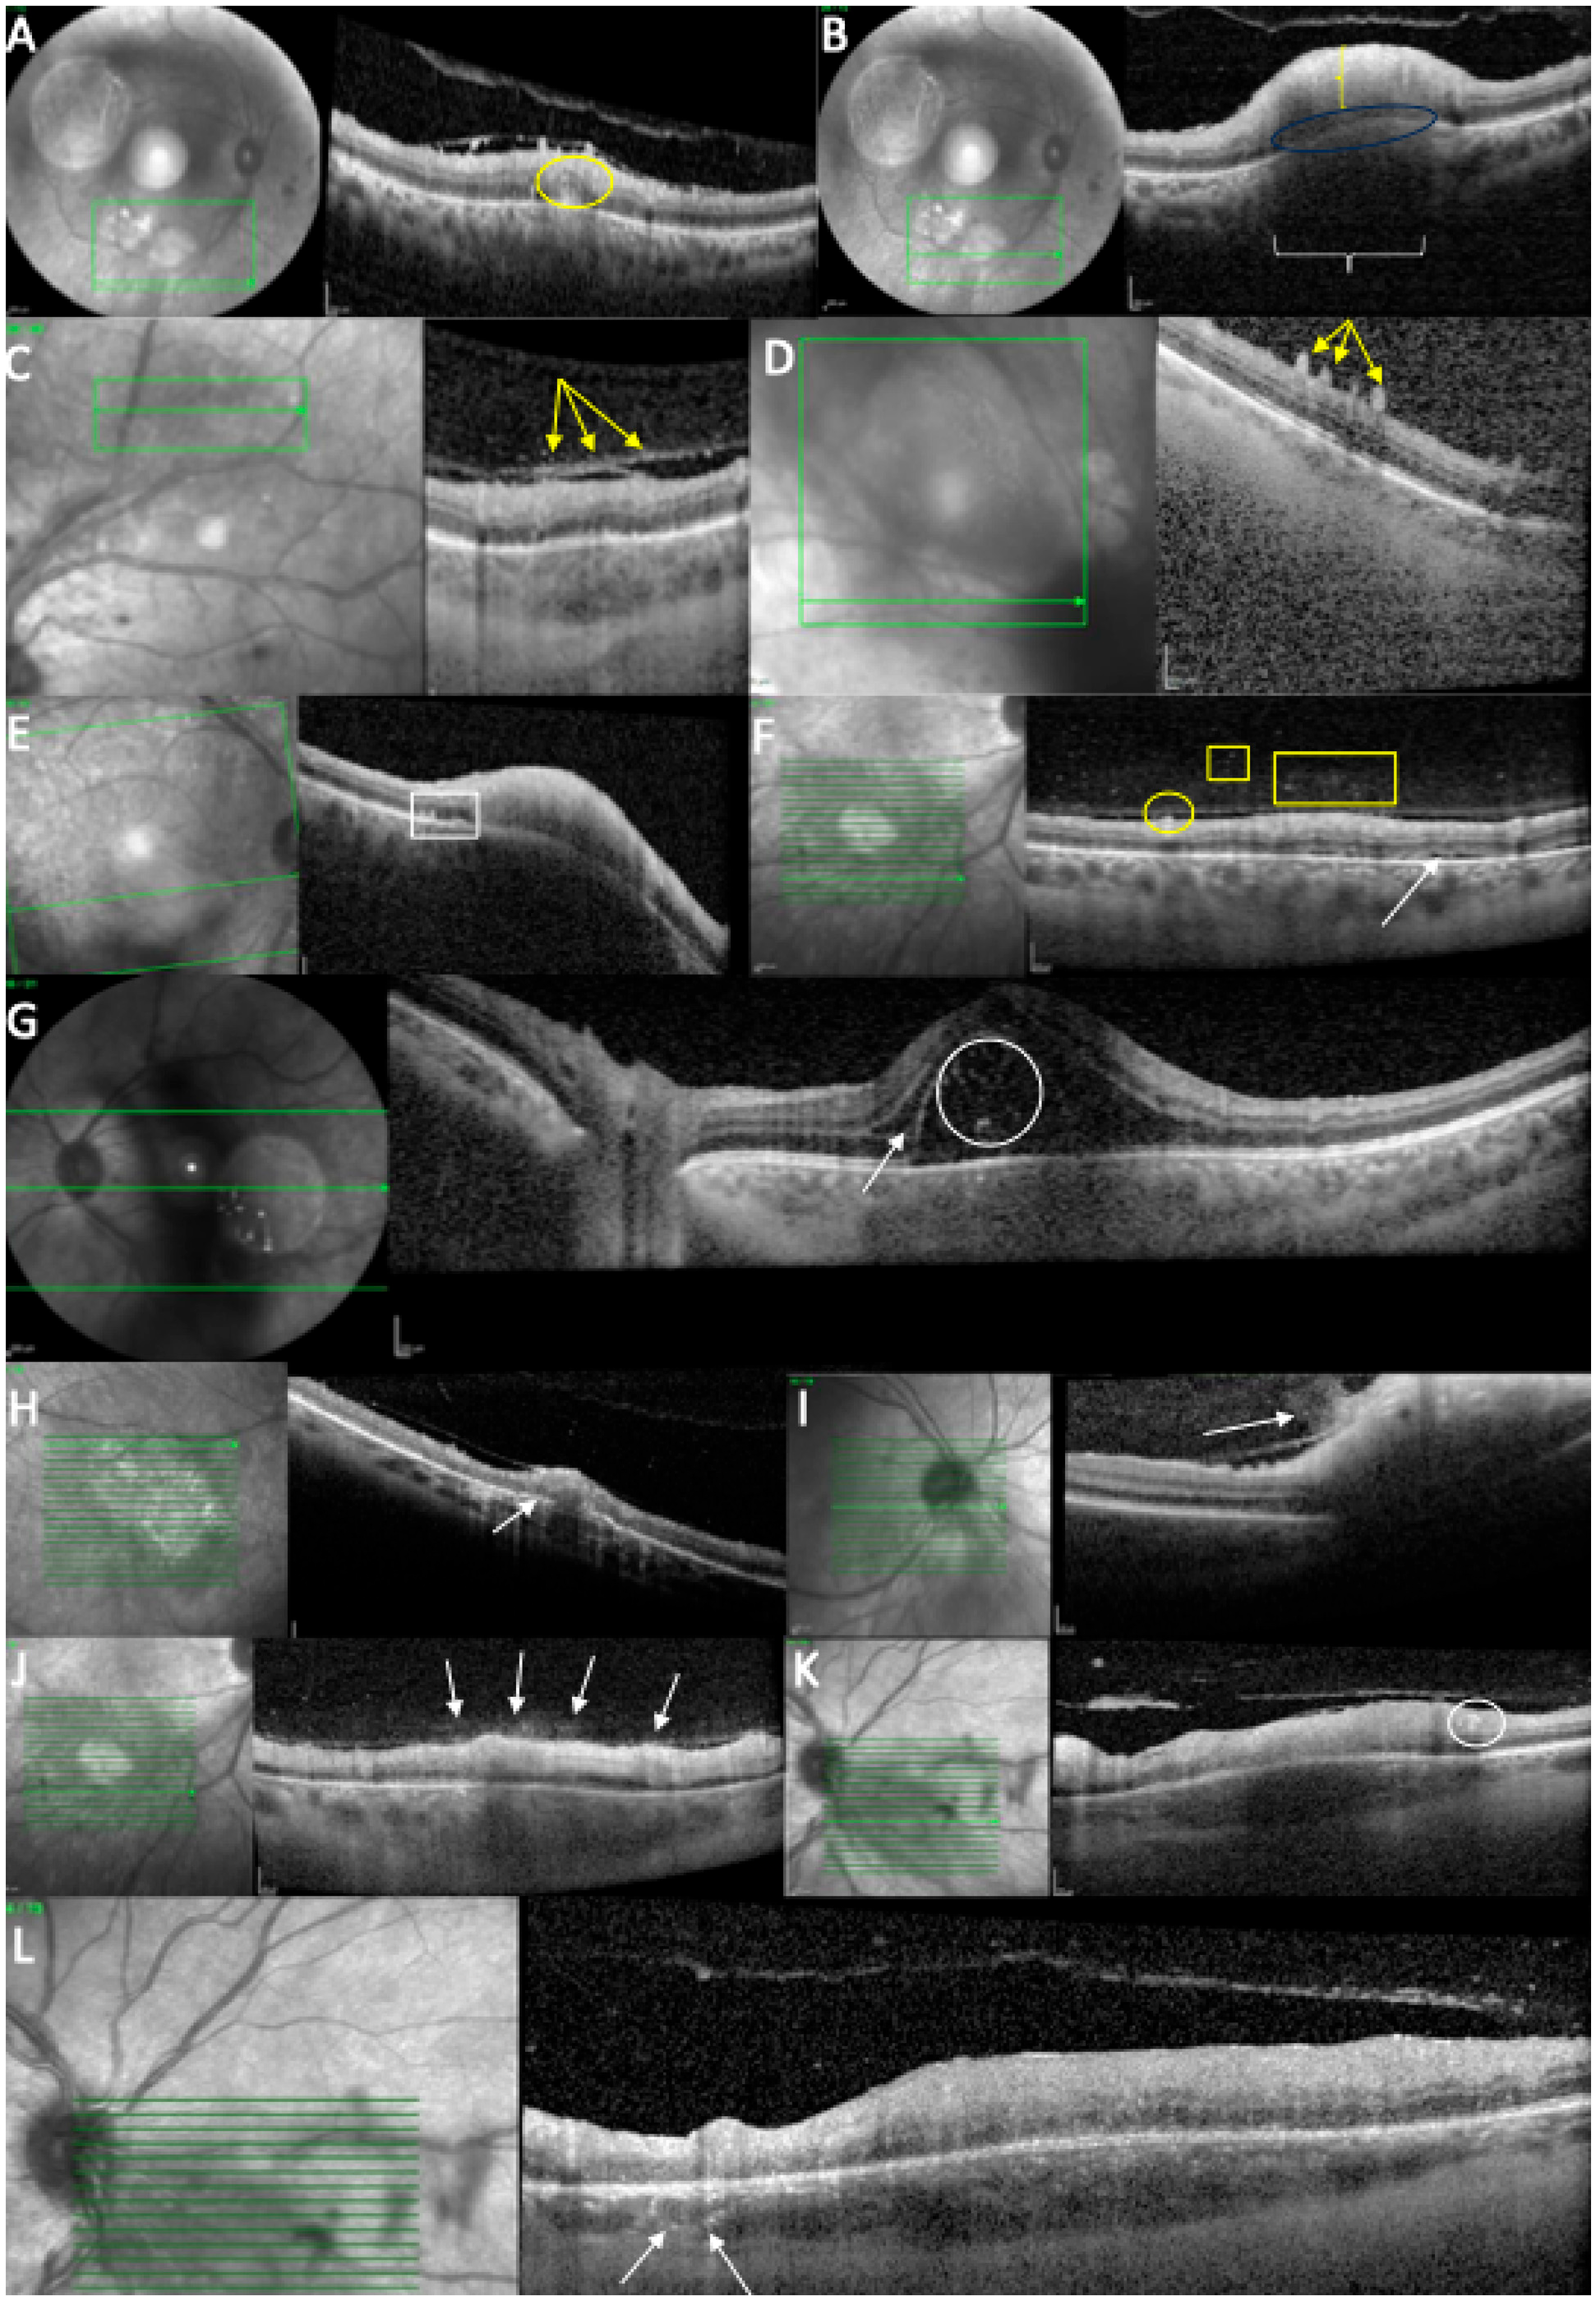

Baseline biomicroscopic findings are summarized in Table 2 (see Figure 3).

At baseline, all cases (12/12 (100%)) demonstrated similar findings of the acute phase, including increased retinal thickness at the level of TRC lesion, and 11/12 (91.67%) cases showed full-thickness hyperreflectivity of the neurosensory retinal layers (see Table 3 and Figure 4). Mean retinal lesions thickness was 522.8 ± 293.5 μm. Disorganized retinal layers adjacent to lesion was a presenting feature in 10/12 (83.3%) lesions. Intraretinal OPL and ONL hyperreflective dots were a common presenting feature in 11/12 (91.67%) cases, adjacent to or far away from the active lesions. Periarteriolar hyperreflective dots were visible in 4/12 (33.3%) cases, while intraretinal fluid and ONL or OPL cysts were observed in 3/12 (25%) cases. Subretinal fluid was present in 4/12 (33.3%) eyes and subretinal hyperreflective dots in 2/12 (16.7%) eyes. Changes in RPE layer were observed as a thickened RPE in 6/12 (50%) cases, as RPE bumps in 2/12 (16.7%) cases, or as a bowing of retina–RPE–Bruch’s membrane in 7/12 (58.30%) cases. Macular hole was observed in 1/12 (8.35%) eyes. Liquefactive necrosis was already observed at baseline in 3/12 (25%) cases. The interval from symptom onset was 10, 14, and 49 days in these three patients. In terms of choroidal findings, 11/12 (91.67%) active lesions demonstrated significant choroidal thickening beneath the retinal active lesions at the acute phase, coupled with hyporeflectivity of the choroid in 11/12 (91.67%) eyes. Hyperreflective dots around choroidal vessels were also noted in 4/12 (33.3%) eyes. Mean choroidal thickness was 514.1 μm, but due to increased retinal hyperreflectivity, choroidoscleral interface was visible only in 8/12 eyes.

Vitreous SD-OCT findings included hyperreflective vitreous dots in 8/12 (66.66%) eyes. In addition, posterior hyaloid thickening was noted in 8/12 (66.66%) eyes. Hyperreflective vitreous dots were also observed over a blood vessel in 3/12 (25%) eyes while hyperreflective deposits were noted over the ILM in 11/12 (91.67%) eyes or on the posterior hyaloid in 8/12 cases (66.66%).

Figure 4. OCT scan at the time of diagnosis. (A) Intraretinal hyperreflectivities (circle) in the ONL, close to the TRC lesion. (B) Retinal hyperreflectivity (vertical bracket), increased thickness, RPE bowing (ellipse), and choroidal hyporeflectivity (horizontal bracket). (C) Posterior hyaloid hyperreflectivities (arrows). (D) ILM deposits (arrows). (E) RPE bumps (rectangle) and RPE bowing. (F) ILM deposits (circle), hyperreflective vitreous dots (square/rectangle), and subretinal fluid (arrow). (G) Subretinal hyperreflective dots (circle) and intraretinal fluid (arrow). (H) Increased RPE thickness (arrow). (I) “Hairy appearance” (arrow). (J) Hyperreflective dots above the blood vessels (arrows). (K) Hyperreflective dots around a retinal blood vessel (circle). (L) Hyperreflective dots around choroidal vessels (arrows).